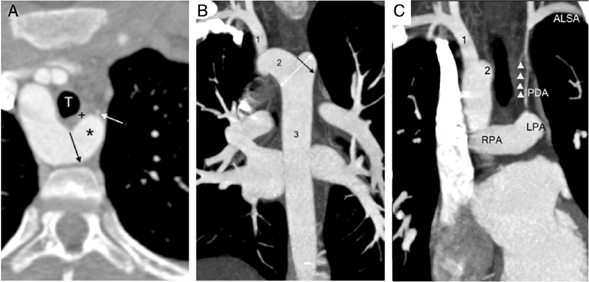

Paciente varón, de 11 años de edad, sin antecedentes patológicos de importancia, quien acudió por dolor torácico retroesternal leve, tipo opresivo, de presentación esporádica (una vez al mes), después de la ingesta de alimentos sólidos; negó síncope. Clase funcional I. Al examen físico: exploración cardiaca normal, presión arterial: brazo derecho 105/65 y en brazo izquierdo 95/60; leve disminución de pulso radial izquierdo (respecto al derecho) con llenado capilar adecuado; miembros superiores simétricos, trofismo adecuado. ECG en ritmo sinusal, en límites normales. La ecocardiografía reveló arco aórtico a la derecha y vasos supraaórticos de difícil evaluación; no se encontró ningún defecto congénito asociado. La tomografía confirmó arco ártico derecho con origen de los vasos supraaórticos, así: origen común de ambas carótidas (tronco bicarotídeo), seguido de subclavia derecha, y en el arco distal presenta dilatación tipo divertículo de Kommerell, con las siguientes medidas: base 14 mm de diámetro (figs. 1 A, B) y 26 mm de diámetro, medido desde la pared aórtica opuesta hacia la punta del divertículo de Kommerell (fig. 1B). En la parte anterior y la derecha del divertículo se observa tráquea sin evidencia de compresión o desplazamiento; entre la tráquea y el divertículo cursa esófago vacuo (colapsado), aunque no llega a conformar un anillo vascular completo. Se observa arteria subclavia izquierda de pequeño calibre (2 mm de diámetro), con origen en la rama pulmonar izquierda (en posición de conducto arterioso). El trayecto de su segmento proximal es longitudinal, paralelo a la tráquea, levemente tortuoso y de curso anterior al divertículo, sin compresión del esófago ni de la vía aérea proximal y distal, ya que discurre lejano a ellos; sin embargo, después de dar origen a la arteria vertebral, recupera su calibre, similar a su contralateral (fig. 1C). Para precisar mejor esta anomalía y su abordaje se utilizó una nueva herramienta en el estudio de imágenes médicas, la “impresión en 3D” (figs. 2 y 3).

Figura 1 Tomografía axial computarizada. A. TAC plano axial; se aprecia arco aórtico a la derecha y divertículo de Kommerell (*) con su orificio de entrada o base que mide 14 mm (flecha negra). En su parte anterior se observa subclavia izquierda de pequeño calibre (flecha blanca), esófago(+), tráquea(T). B. Se observa divertículo en vista coronal, el diámetro de su base (flecha negra) y el diámetro desde la pared aórtica opuesta a la punta del divertículo (flecha blanca de doble cabeza). C. Se muestra arteria subclavia izquierda aberrante (ALSA) con origen desde la rama pulmonar izquierda (LPA) a través del conducto arterioso (PDA), con pequeño calibre en su segmento proximal (triángulos), después del origen la vertebral normaliza su diámetro. (1) Arteria subclavia derecha. (2) Arco aórtico transverso. (3) Aorta descendente. (RPA) Rama pulmonar derecha.